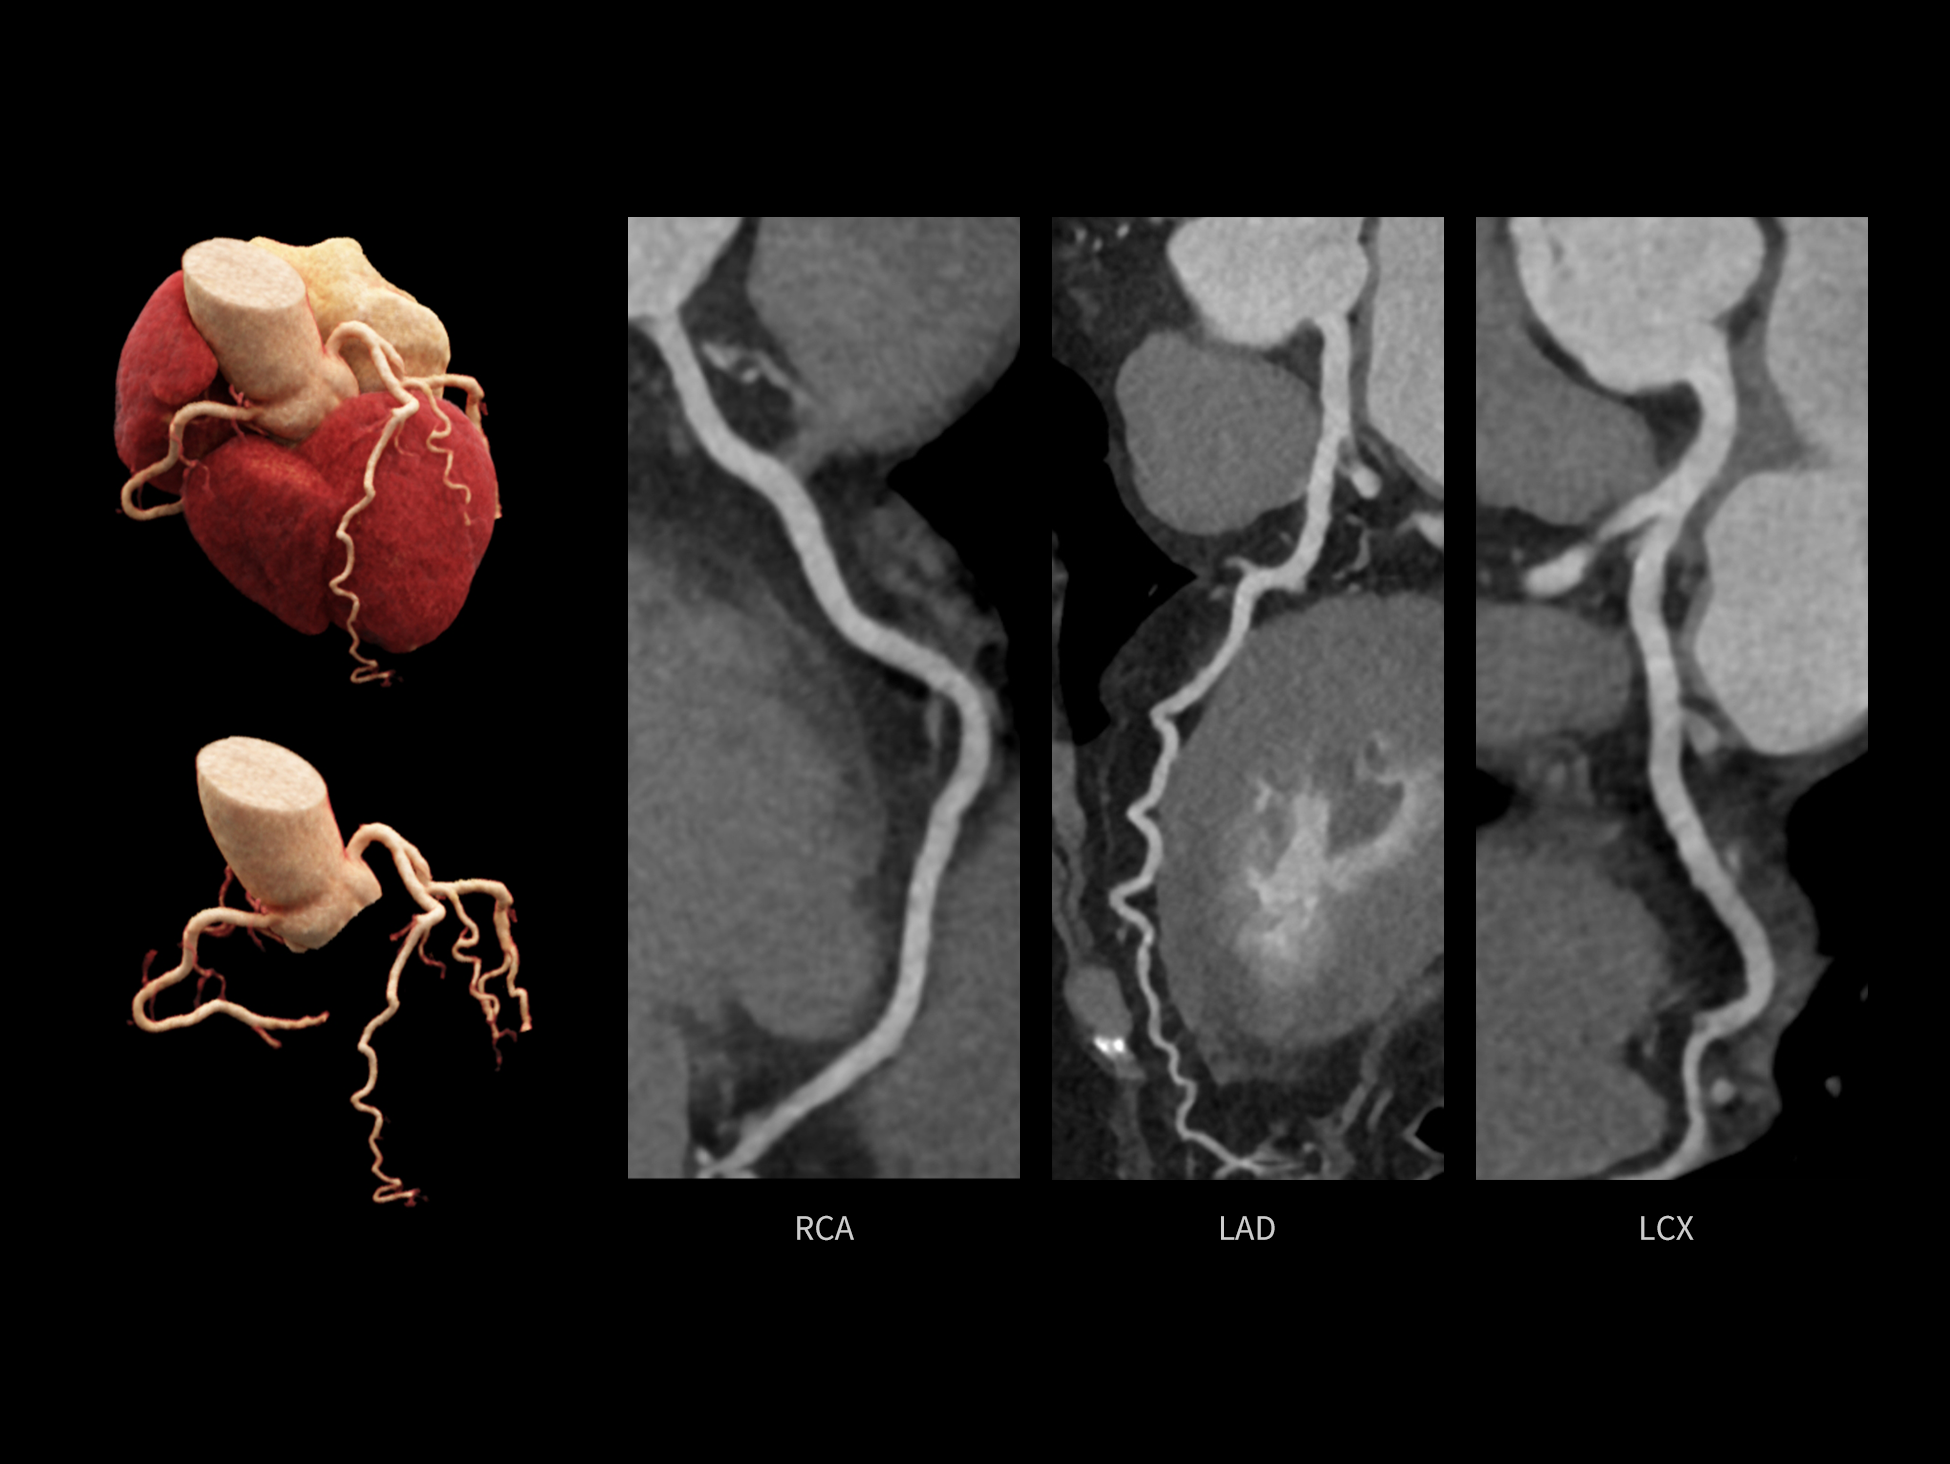

全时心脏

uCT SiriuX® 挑战心脏成像时间分辨率的极限,精准捕捉心脏全周期的动态变化。无论静态解剖形态,还是动态功能表现,都能清晰呈现,让心脏不再是“定格”的器官,而成为可视的生命律动。

CardioCapture 2.0 通过“识别–追踪–建模–校正”的完整流程,精准分割心脏结构,动态追踪运动轨迹,并构建多时相运动场,最终实现冠脉、瓣膜、心肌及心室结构的同步校正,清晰洞见每一次心跳细微变化,真正将心脏动态掌握于毫秒之间。

CardioCapture 2.0 在目标时相前后重建多时相影像,通过深度学习网络精准提取冠脉中心线,进而建立时相间运动模型,实现对冠脉分段图像的精准运动校正。

CardioCapture 2.0 可对心肌、瓣膜及心室等结构进行同步运动校正。基于深度学习的心脏精细分割,实现了更完整的心脏全局信息提取,能有效抑制全心运动伪影,显著提升心脏细节的清晰度与诊断可靠性。

8ms 全心等效时间分辨率

冠脉运动校正

全心结构运动校正

心脏成像,自由掌控